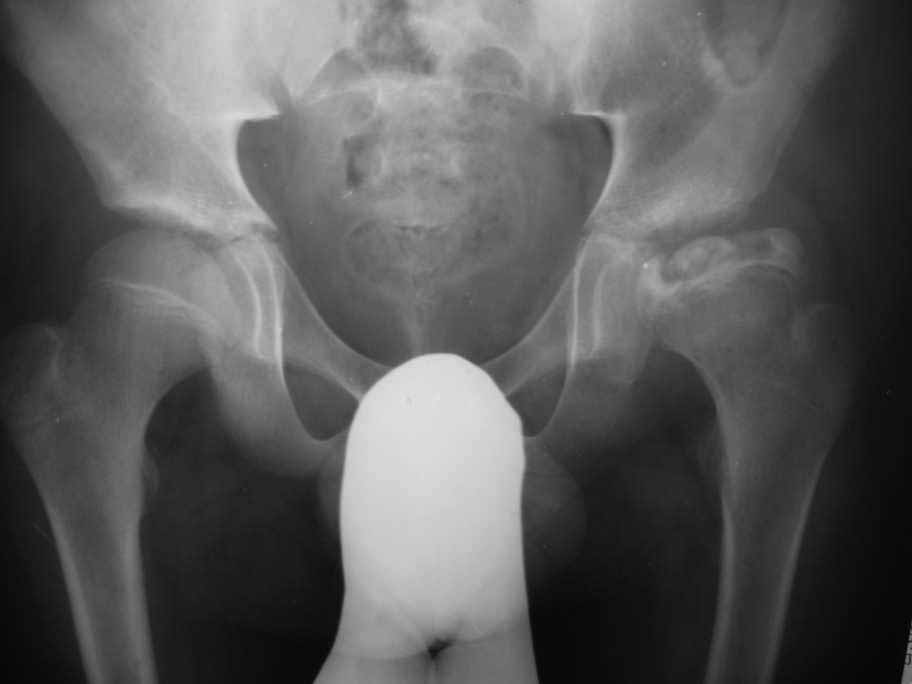

Здравствуйте уважаемые коллеги, Посоветуйте, пожалуйста, тактику лечения для пациента с

болезнью Пертеса. Мальчик 14- ти лет обратился с жалобами на боли в левом тазобедренном

суставе. Болеет около шести месяцев

Клинически : Движения в суставе ограничены ,сгибание 90

гр, отведение -30гр,ротационные движения 5-0-5 гр. Спасибо Ihor